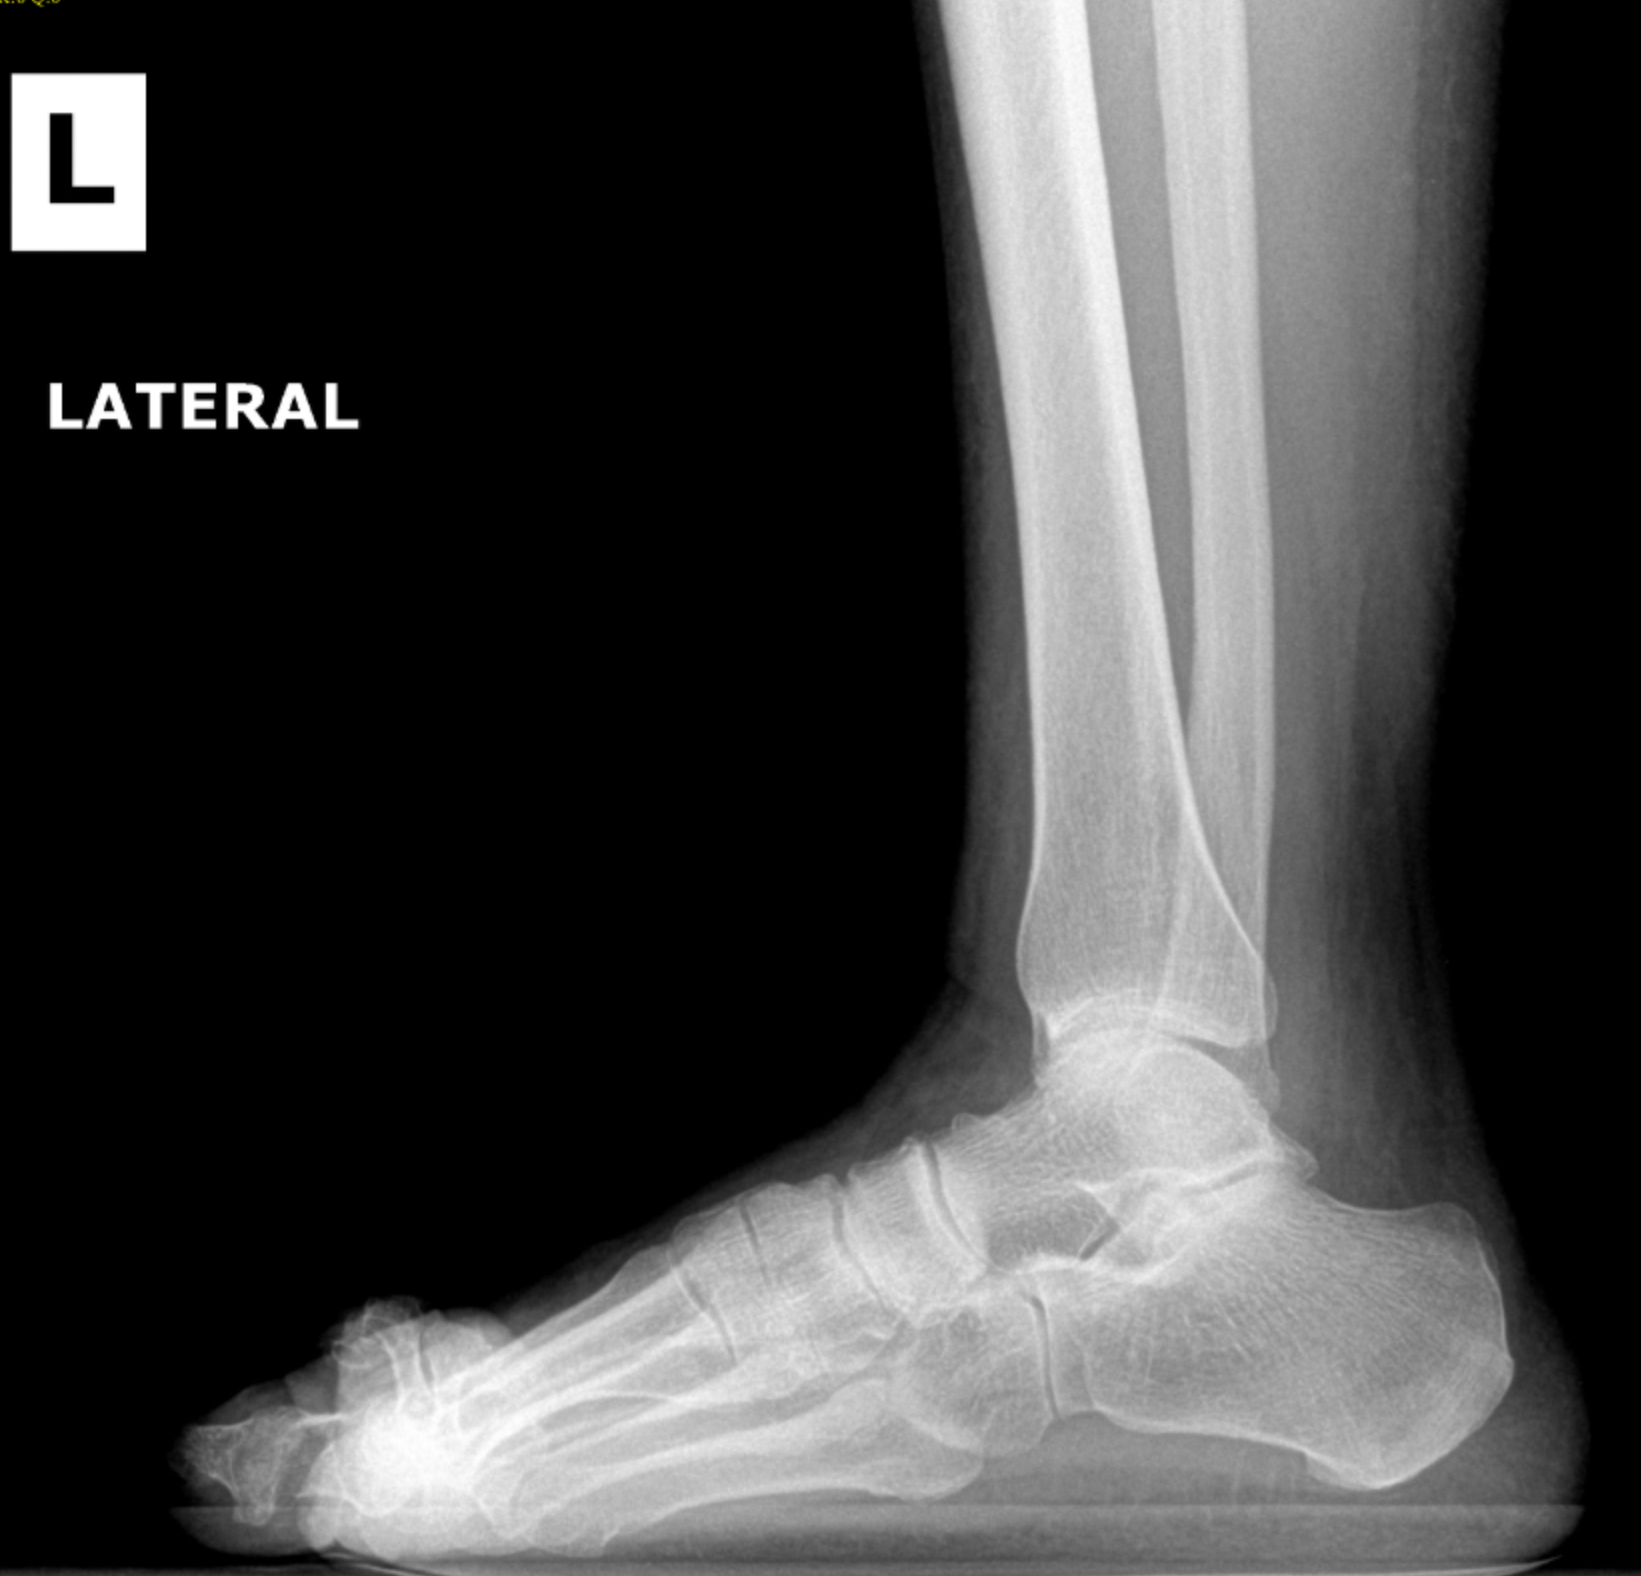

Pre-op XR Images